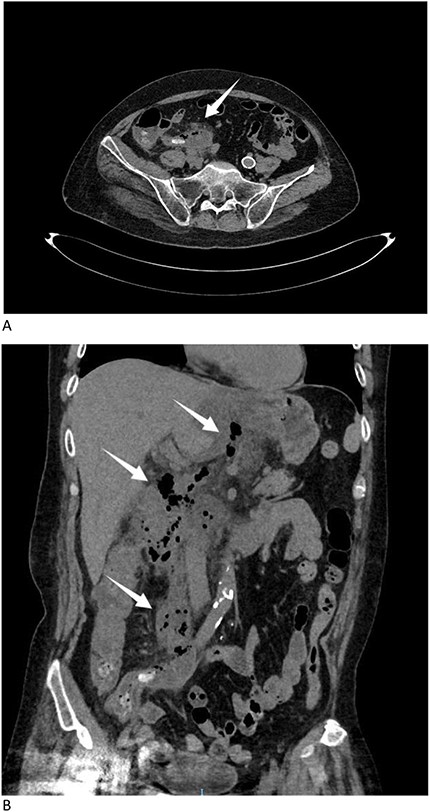

A 57-year-old male presented to the emergency department with gradually increasing right-sided abdominal and back pain, accompanied by a fever of 39.6°C for the past 8 days. He was initially evaluated at a local hospital where ultrasound revealed perforation. He was subsequently admitted to our hospital. Physical examination revealed abdominal tenderness. The patient had no significant medical history. Laboratory tests showed a white blood cell count of 20.8 × 109/L and elevated C-reactive protein levels of 147.1 mg/L, indicating sepsis. Other laboratory data also showed hyponatremia, hypokalemia, and hypoproteinemia due to poor appetite following the onset of symptoms. Immediate computed tomography (CT) scan identified an appendicolith with diffuse infiltration (Fig. 1A), and a large amount of gas was observed in the retroperitoneal space, extending from the cecum along the mesentery to the stomach (Fig. 1B). The patient was diagnosed with retroperitoneal perforation.

(A) CT scan identified an appendicolith with diffuse infiltration (arrow). (B) CT scan showed a large amount of gas in the retroperitoneal space, extending from the cecum along the mesentery to the stomach (arrows).